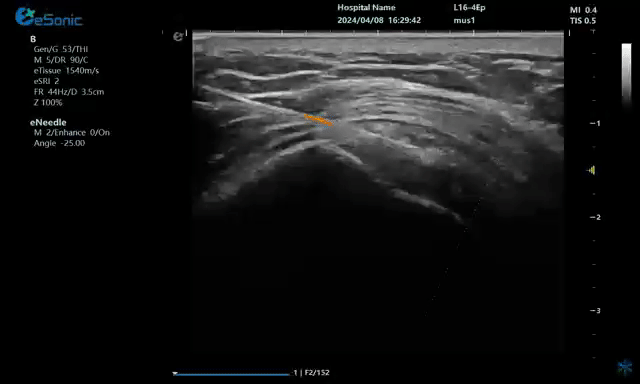

无磁导航技术引导穿刺钙化点